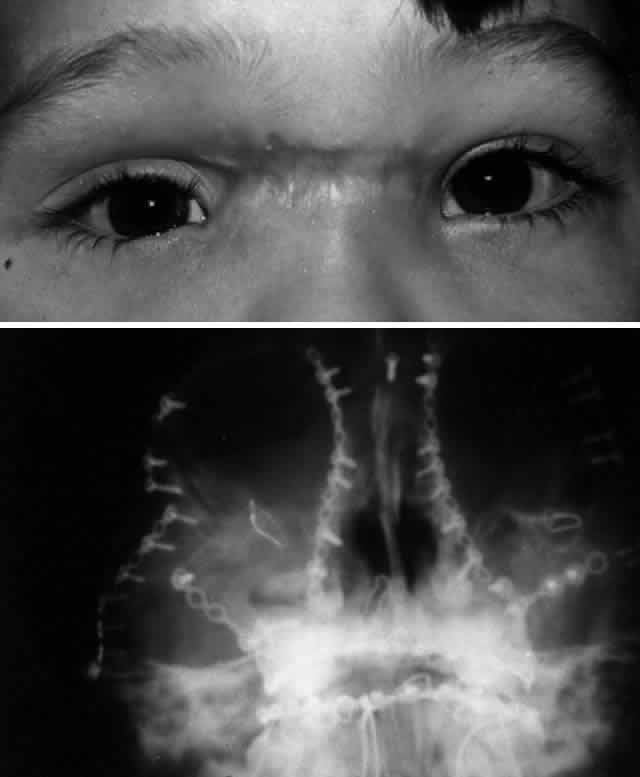

The position of the globe is also assessed (Fig. 3). As detailed previously, outward expansion of the orbital walls (blow-out fractures) can produce enophthalmos. Inward expansion of the orbital walls (blow-in fractures) can reduce orbital volume, potentially producing exophthalmos. In the early period after blunt orbital trauma, orbital edema and hemorrhage can transiently increase the orbital soft tissue volume, producing exophthalmos or “masking” the underlying potential for enophthalmos. As orbital edema subsides, the true globe position becomes evident. Over a more extended period of time (several months), soft tissue changes (cicatrization and, less commonly, fat atrophy) may contribute to the production of late enophthalmos. Globe position can be grossly assessed by direct visual inspection. Viewing the axial projection of the globes from above (“bird's-eye view”) or from below (“worm's-eye view”) facilitates a gross determination of axial globe position.

Fig. 3. A. Patient with blunt left orbital trauma demonstrates moderate enophthalmos of left eye (note deep superior sulcus). B. Slight restriction of supraduction in the left eye.

After the history and physical examination, consideration is given to further assessment of the orbital injury with radiologic imaging. The indications for radiologic imaging area are based on the physician's assessment of the injury and include gross orbital and facial deformity, limitation of ocular motility, and associated neurologic injuries. CT is the imaging modality of choice in the assessment of orbital/craniofacial fractures because it provides excellent detail of the bony injury as well as the orbital soft tissues in most cases (Fig. 4). Ideally, both axial and direct coronal views are preferred. Coronal views are necessary for adequate imaging of the orbital floor and orbital roof. With direct views, 3-mm views (cuts) are usually adequate. In cases in which the patients cannot be positioned for direct coronal imaging, coronal reconstructions can be performed, provided that finer (1.5-mm) axial cuts are used. Reconstructed coronal images lack the resolution of direct coronal images, but they are usually adequate when direct coronal imaging cannot be obtained. Spiral CT, which allows rapid imaging and multiplanar formatting, will likely become useful in the assessment of orbital trauma as this newer technology becomes increasingly available.

Fig. 4. Same patient as depicted in Figure 3. A. Water's view. Facial x-ray shows ill-defined left inferior orbital floor fracture with soft tissue mass in superior left maxillary sinus. B. Coronal CT scan shows superior resolution of left orbital floor defect, with prolapse of orbital soft tissues into the maxillary sinus. Note distortion of left inferior rectus muscle. Floor defects greater than 50% are more likely to produce enophthalmos.

Before CT scanning was readily available, facial x-ray series were used in the radiologic assessment of orbital fractures. Typical views included Caldwell's (anteroposterior) view, Waters' view, lateral view, and submental vertex view (particularly good for viewing the zygomatic arches). Waters' view, which is obtained with the chin slightly elevated, is considered the most useful x-ray view for imaging the orbital floor, inferior rim, and maxillary sinus. Because CT scans are superior to x-rays in terms of sensitivity and reliability, in most situations today plain orbital/facial x-rays are obtained only when a CT scan is unavailable or when only very minimal injury is suspected. Magnetic resonance imaging (MRI), although able to image orbital soft tissue exquisitely well with a small surface coil, is generally of limited usefulness in the initial assessment of orbital/craniofacial injuries because of its limited ability to image bone. It is contraindicated in cases of suspected retained ferromagnetic foreign bodies. MRI may have a secondary role in the management of orbital trauma in cases where CT scanning suggests the presence of soft tissue injury, such as intramuscular hemorrhage or sub-dural optic nerve sheath hemorrhage. In such cases, the better soft tissue resolution potentially available with MRI may allow more specific diagnostic interpretation.2